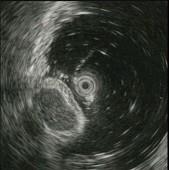

问题 患者,男,59岁,上腹不适2周,查体:心肺腹未见异常。电子胃镜图片及超声内镜如下,进一步要做的最佳治疗方案为 ( )

选项 A.电子胃镜下切除 B.外科手术切除 C.电子胃镜联合腹腔镜切除 D.随访观察 E.口服抗肿瘤药

答案 C